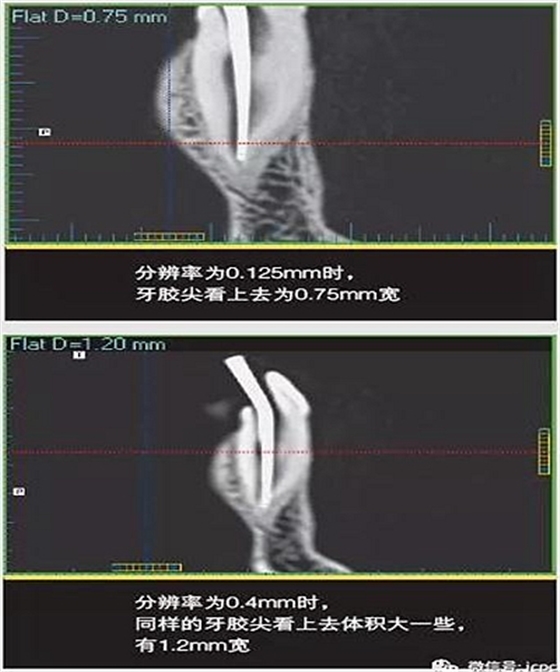

如果探測器中一個(gè)高對(duì)比度物體的體積小于體素尺寸,則該對(duì)象將會(huì)有效地填充入整個(gè)體素,使其看起來比實(shí)際物體大。牙膠周邊碎片的顯影就是其中一個(gè)很好的例子,如果牙膠周邊碎片的體積小于體素大小,則圖像上會(huì)看起來比實(shí)際的大。